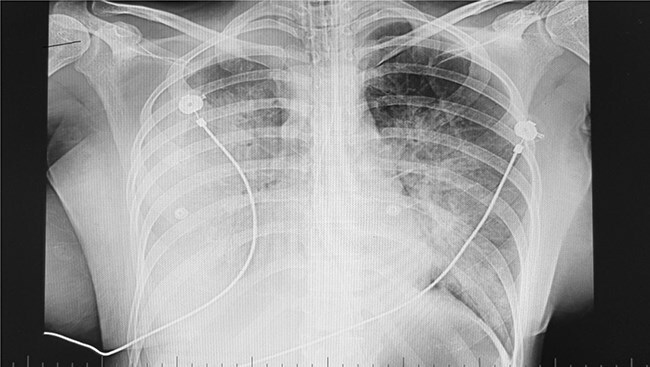

Case report: A 26-year-old woman with postpartum cardiomyopathy was admitted to Razi Hospital with abdominal pain, dizziness, nausea, and vomiting. She was diagnosed with poisoning from local mountain mushrooms and transferred to the ICU due to low blood pressure, elevated enzymes, and tachycardia. Echocardiography showed severe cardiac dysfunction (EF = 25%), and she developed severe tachycardia, decreased consciousness, and metabolic-respiratory acidosis. After dialysis and treatment with NAC infusion for 7 days, her consciousness improved, she was extubated, and EF increased to 40%.